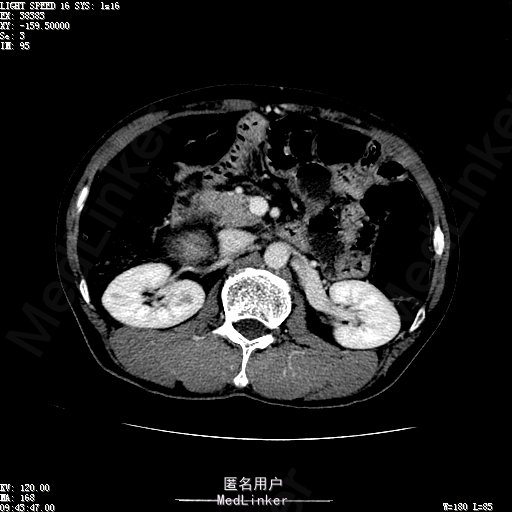

查体:体温36.4℃,脉搏76次/分,呼吸18次/分,血压110/70mmHg。神志清晰,发育正常,营养中等,体位自如,表情安静,慢性病容,检查合作。皮肤粘膜颜色正常,无瘀点、紫癜,有肝掌,无蜘蛛痣,无水肿,毛发的生长与分布正常。浅表淋巴结浅表淋巴结未触及肿大。无巩膜黄染,结膜正常。口唇红润,粘膜正常,舌正常,牙龈正常,扁桃体无肿大,无咽部充血。颈部外形对称,颈静脉正常,肝颈静脉回流征阴性,气管居中。甲状腺正常,无颈部血管杂音。胸部形态正常,呼吸运动平稳规律,无呼吸困难,肋间隙正常。触诊语颤正常,无胸膜摩擦感,肺下界位于右锁骨中线第六肋间。呼吸音正常,未闻及干湿啰音,无胸膜摩擦音。无心前区隆起,心尖搏动正常,心率:76次/分,心律齐,心音正常,无杂音,无心包摩擦音。无大动脉及周围血管征,无奇脉及交替脉,无水冲脉,无枪击音,腹型对称,无腹壁静脉曲张,未见胃肠型及蠕动波,无瘢痕,脐部正常。无压痛,无反跳痛,无腹肌紧张,无腹部包块。肝未触及,Murphy征阴性,脾未触及,肾未触及,无移动性浊音。无肝区叩击痛,无肾区叩击痛,无脾区叩击痛。肠鸣音正常4次/分,无气过水声。外阴及肛门:未查。四肢正常,关节正常,无下肢水肿,无下肢静脉曲张,无杵状指趾。 辅助检查:彩超:肝表面欠光滑,肝内占位5.2*5厘米 ct如下图

诊断:乙肝肝硬化 代偿期 原发性肝癌。 患者病史明确,目前化验转氨酶轻度升高,说明有活动性肝损伤,白蛋白降低提示肝脏合成代谢功能下降,AFP从一年前至今逐渐升高,提示活性肿瘤细胞增多。CT所见明确诊断肝癌,并有周围卫星灶,应近期行TACE治疗。 处置:DSA下肝动脉造影及TACE 手术简要经过:患者平卧位,术区皮肤消毒,铺手术巾,2%利多卡因局麻后,Seldinger法穿刺右股动脉,入血管鞘,5F猪尾管腹主动脉造影,超滑导丝yidao5F RH管腹腔干、肠系膜上动脉、左肾动脉分别造影,腹腔干造影时,见肝右叶7-8处小结节样肿瘤染色,未见外凸生长较大病灶染色。微导管超选肝右动脉注入三氧化二砷碘油混悬液10毫升,横结肠遮挡部位见较大病灶有伞状碘油沉积。复查造影未在见肿瘤染色,拔出导管和血管鞘,穿刺处压迫止血,加压包扎。术毕。

患者术后8天来,无不适,无发热,无腹痛和腹胀,无恶心呕吐,食欲睡眠好,尿便正常。 查体:神志清,巩膜无黄染,心肺听诊无异常,腹软,无压痛,肝脾肋下未触及,移动性浊音阴性,双下肢无浮肿。 复查化验结果:丙氨酸氨基转移酶 116 U/L、天门冬氨酸氨基转移酶 41 U/L、胆碱酯酶 1995 U/L↓、总蛋白 56.3 g/L、白蛋白 25.9 g/L。白细胞计数 5.8 10^9/L、红细胞计数 3.18 10^12/L、血小板计数 175.0 10^9/L、*血红蛋白 83 g/L、血小板分布宽度 15.7 、血小板压积 0.175 %、*红细胞压积 24.6 %、平均红细胞血红蛋白 26.1 pg、平均红细胞血红蛋白浓度 337.0 g/L、平均红细胞体积 77.5 fL、平均血小板体积 10.0 fL、嗜碱性粒细胞百分比 0.4 %、嗜碱性粒细胞数量 0.02 10^9/L、中性粒细胞百分比 70.4 %、中性粒细胞数量 4.10 10^9/L、嗜酸性粒细百分比 2.1 %、嗜酸性粒细胞数量 0.12 10^9/L、单核细胞百分比 12.2 %、单核细胞计数 0.7 10^9/L、淋巴细胞数量百分比 14.9 %、淋巴细胞计数 0.9 10^9/L。甲胎蛋白 23564.00 ng/mL 患者术后第8天开始行FOLFOX6化疗。CT上可见明显碘油沉积,术后甲胎蛋白下降治疗有效。嘱患者术后必须定期复查